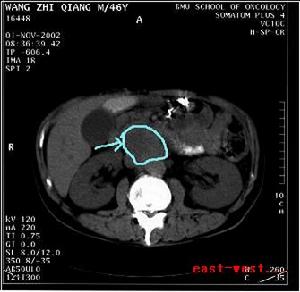

4.CT對診斷後腹膜腫瘤有重要意義:能提供腫瘤位置、範圍和對鄰近組織影響的資料,還能提示腫瘤中心囊性變性(如平滑肌肉瘤),有時能提示特殊的組織學診斷(如脂肪肉瘤、脂肪瘤),並能發現後腹膜正常的及異常的淋巴結。

原發性腹膜後腫瘤--CT2.做好暫時阻斷腹主動脈和髂血管的準備。